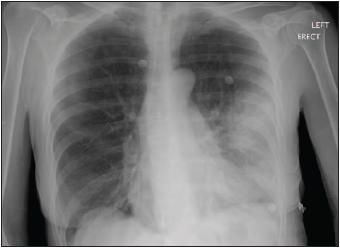

During the initial examination, the patient's temperature was 39.9C (103.9F). Her pulse rate was 104 beats per minute. Blood pressure was 124/74 mm Hg, respiration rate was 24 breaths per minute. Arterial blood gas analysis on admission showed significant hypoxemia (pH was 7.44, PaCO2 was 34 mm Hg, PaO2 was 39 mm Hg, bicarbonate level was 23 mEq/L, and oxygen saturation was 76% on room air). The leukocyte count was 7100/?L, and it increased to 15,200/?L, with 40% bands, in 48 hours. Results of the basic metabolic panel, coagulation profile, and liver function tests were normal. Chest auscultation revealed decreased breath sounds in the left lung base and dullness to percussion in the left midlung. A chest radiograph showed increased density in the left lingular area and a small left pleural effusion (Figure 1). ACT scan of the chest showed a lingular infiltrate with compressive atelectasis and left pleural effusion (Figure 2). A 2-dimensional echocardiogram showed no vegetations. The patient was given moxifloxacin 400 mg IV daily and aztreonam 2 g IV q8h.

Figure 1 -

Aposteroanteriorradiographic viewof the chest showsincreased densityin the lingulararea and a smallleft pleuraleffusion.